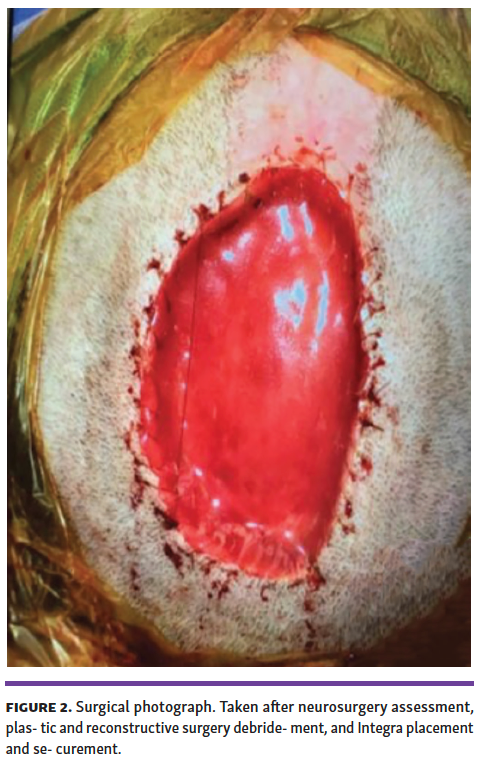

C.W. a 39-year-old woman, mother of 5, with a history of depression who presented with an enlarging full-thickness right paramedial scalp wound. (Figure 1). Over the past year, the patient was noted by multiple family members to be compulsively picking her scalp until she finally presented by the urging of her mother with exposed calvarium. Social history was pertinent for mothering 5 children along with multiple pets at home including cats and a bearded dragon. Psychiatry, neurosurgery, and plastic and reconstructive surgery (PRS) were consulted. Her depression had been worsening, but she had not sought out any additional treatment. Psychiatry diagnosed her with body-focused repetitive behavior (BFRB) disorder, starting her with fluoxetine and cognitive behavioral therapy (CBT). Neurosurgery denied indication to intervene, as the calvarium was intact and there were no neurological deficits. PRS then performed a 2-stage reconstruction of the 6 x 8-cm defect. Stage 1 included debridement, bone burring and placement of a dermal matrix template, and negative pressure wound therapy (NPWT) (Figure 2). Stage 2 took place 5 weeks later with placement of a meshed split-thickness skin graft (Figure 3). Reconstruction was successful, and the patient is doing well amidst ongoing psychiatric challenges (Figure 4).